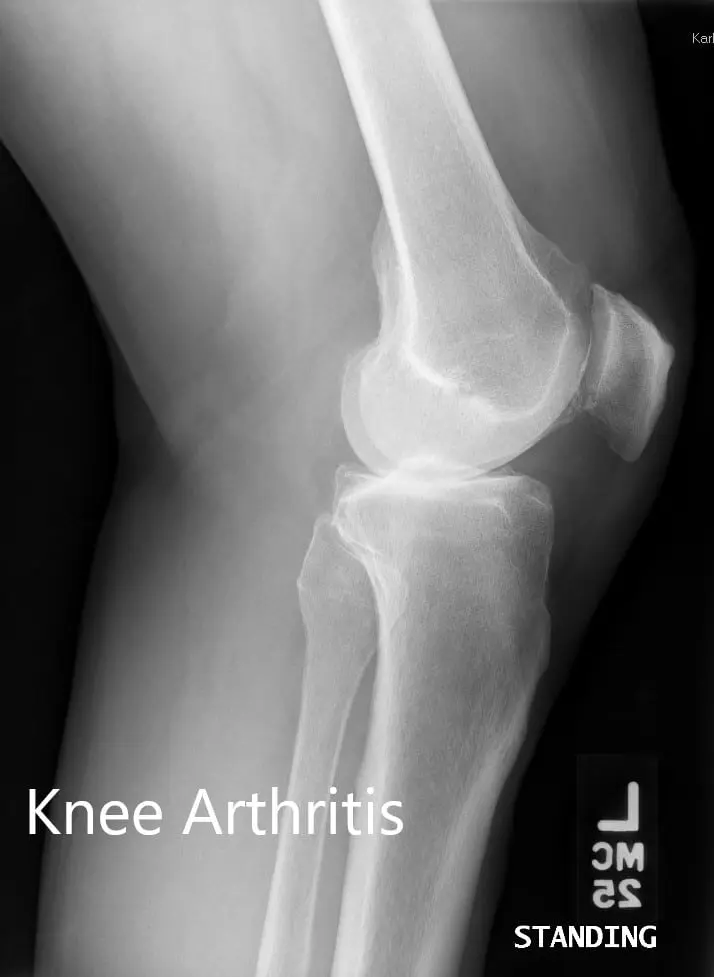

Her imaging studies of both the knee revealed severe tricompartmental osteoarthritis. Considering her lifestyle limiting knee pain, she was advised bilateral custom total knee replacement. Risks, benefits, and alternatives were discussed with the patient at length. She agreed to go ahead with a bilateral custom knee replacement.

Preoperative X-ray showing the lateral views of the right and the left knee respectively

Preoperative X-ray showing the lateral views of the right and the left knee respectively.Complete Orthopedics patient specific surgical plan for a Bilateral Customized Total Knee Replacement in a 72-year-old patient with Arthritis